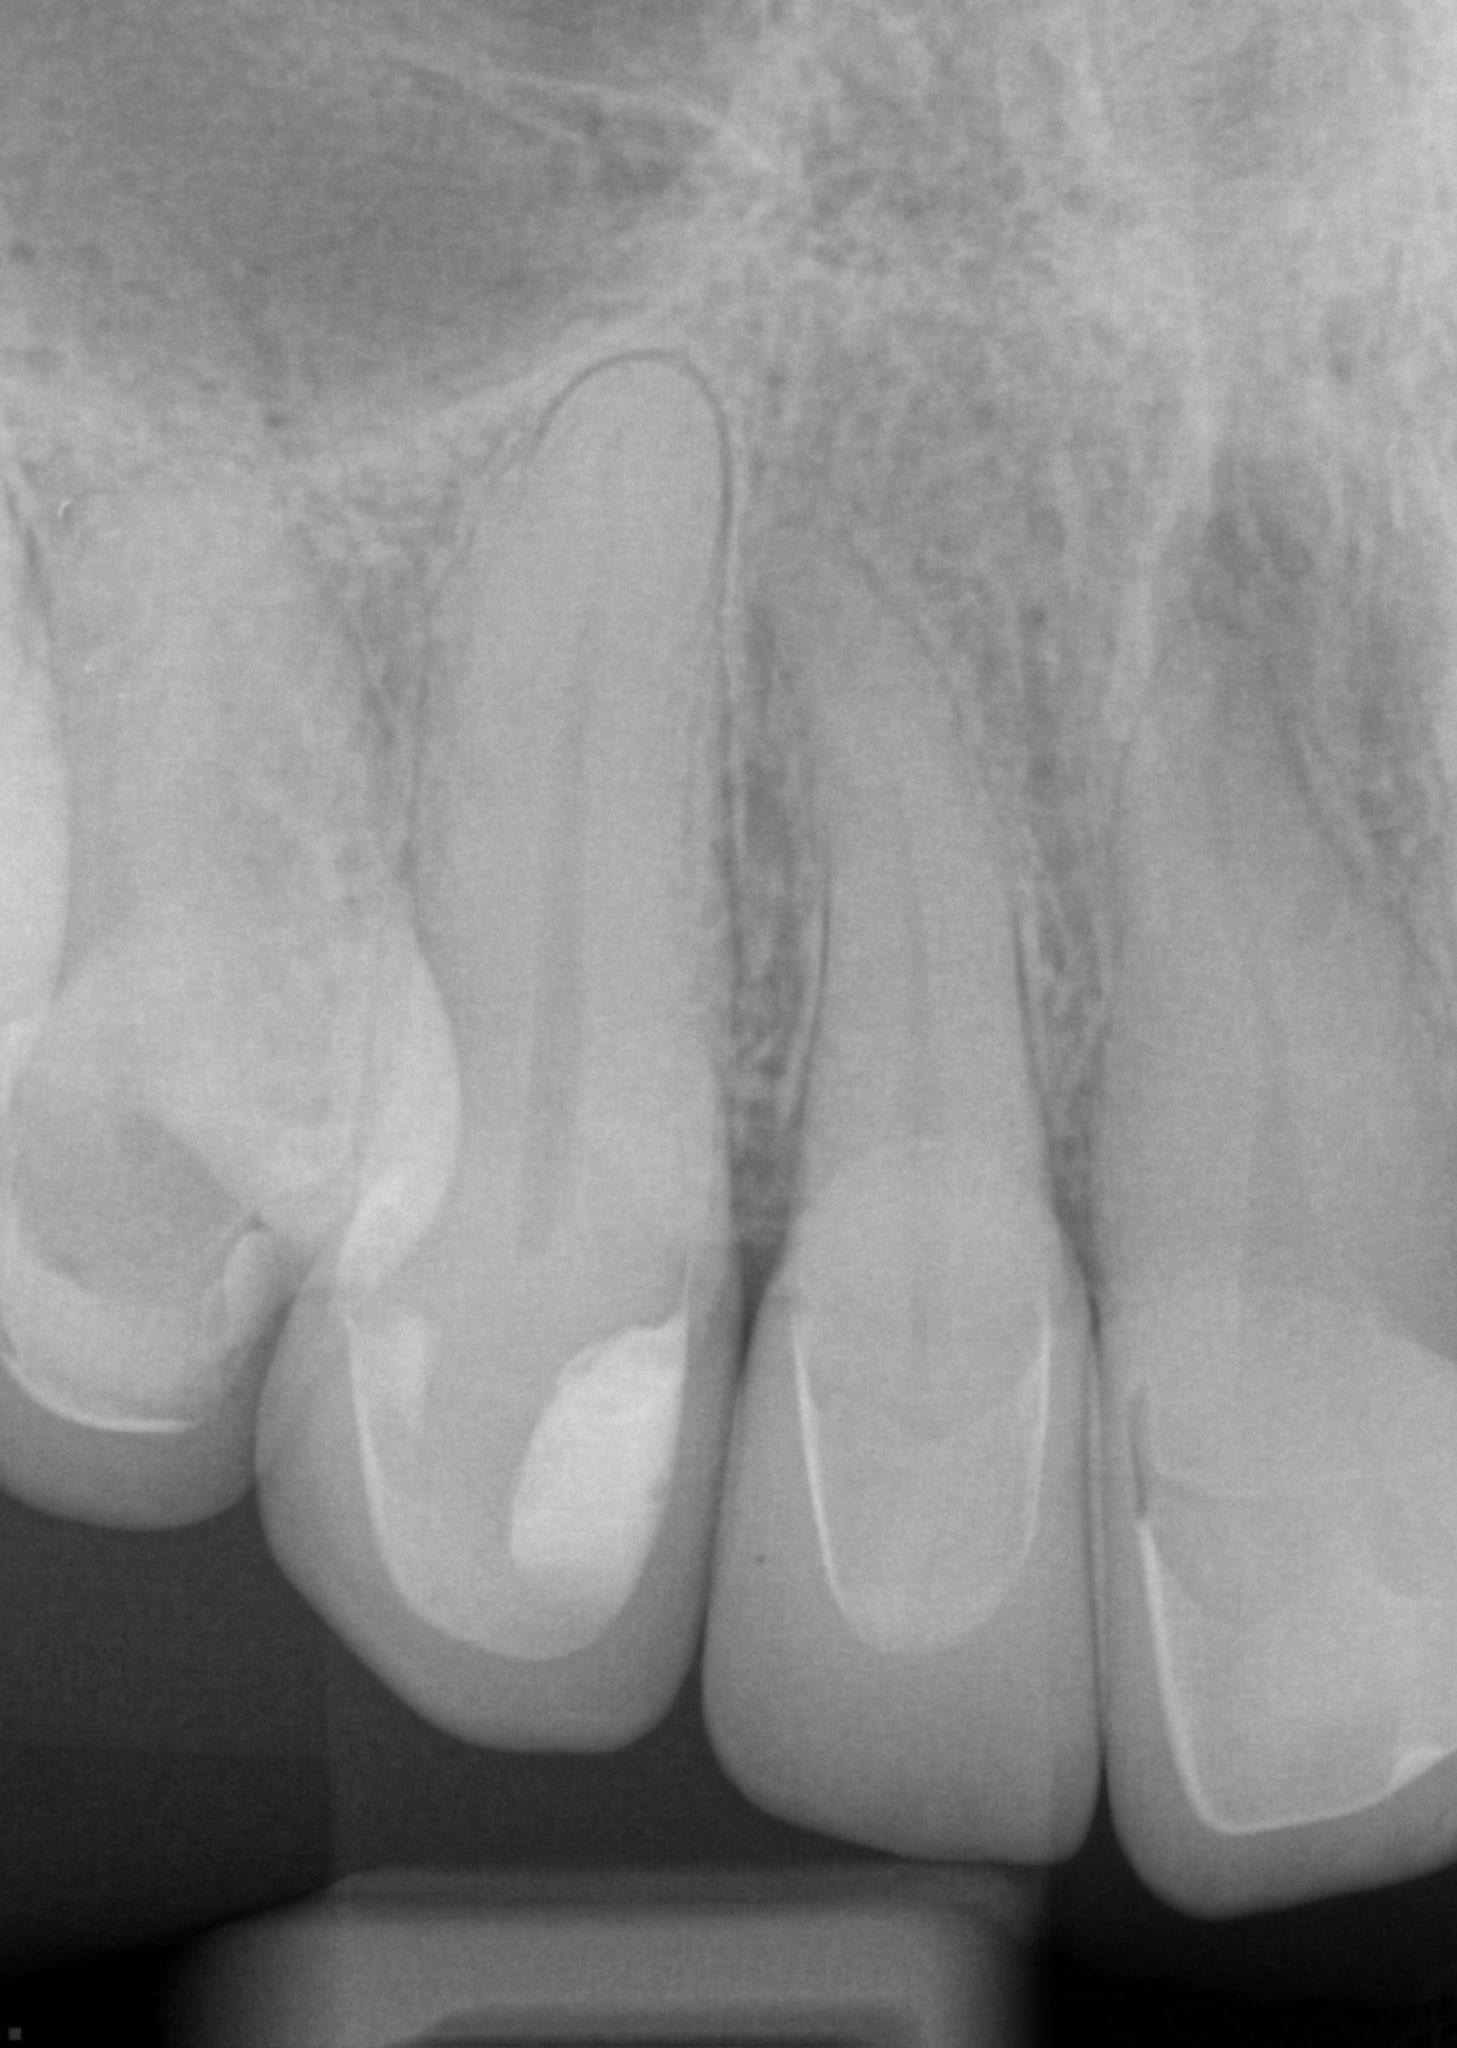

One Month Post Op with Radiographs